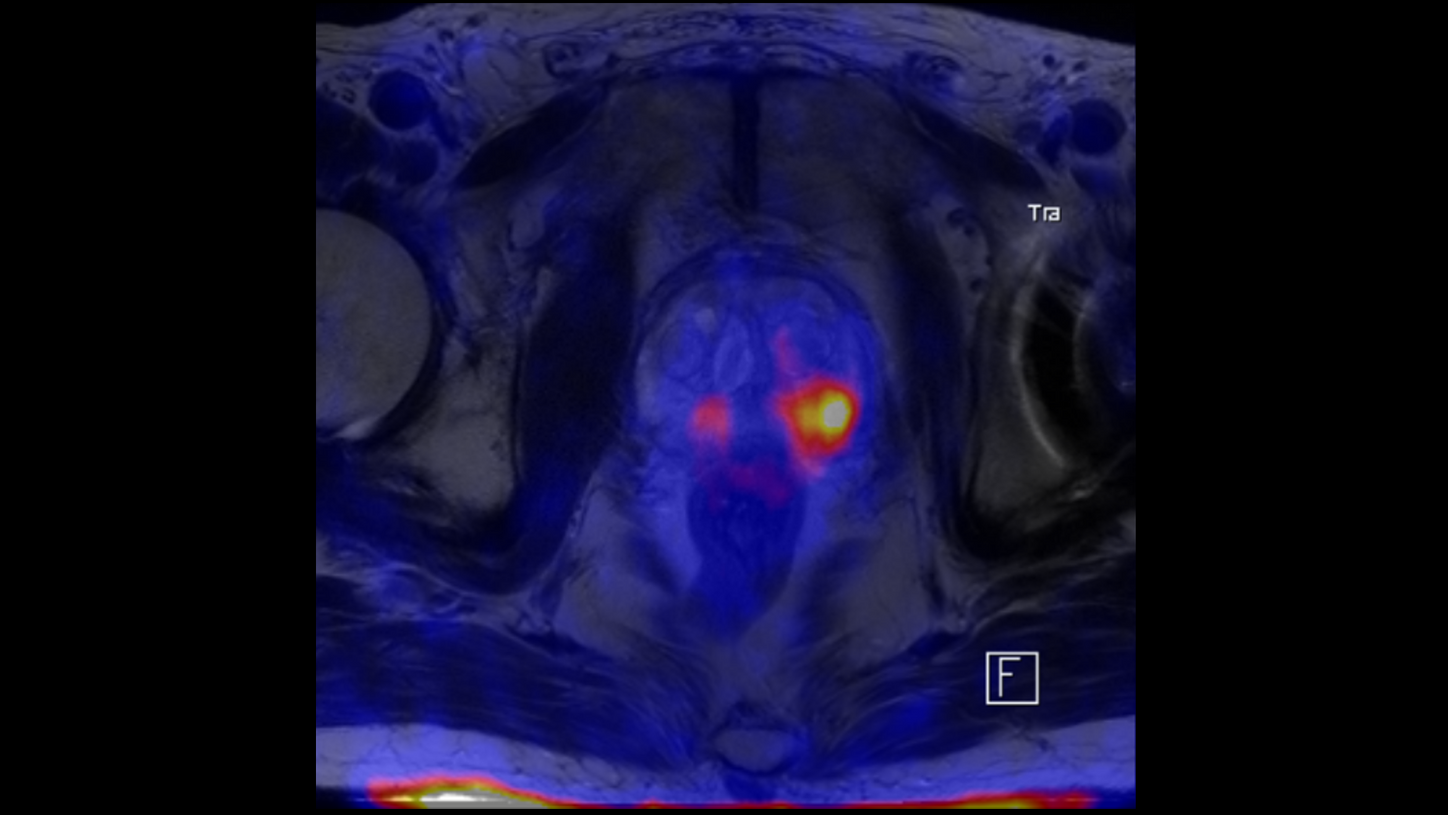

Theranostics and other novel drug therapies make truly targeted treatments possible for the very first time. To realize this potential, an imaging system is needed that shortens patients’ pathways to a precise diagnosis and timely treatment.

Introducing BIOGRAPH One* – the game-changing PET/MR scanner designed to shape a new era for one simplified patient-centric pathway.

BIOGRAPH One is designed to support one patient-centric pathway to personalized care. By seamlessly integrating PET and MR into one comprehensive exam, it will support clinicians from diagnosis and staging, through a personalized therapy decision to regular therapy assessments to excel precision and support one streamlined approach.